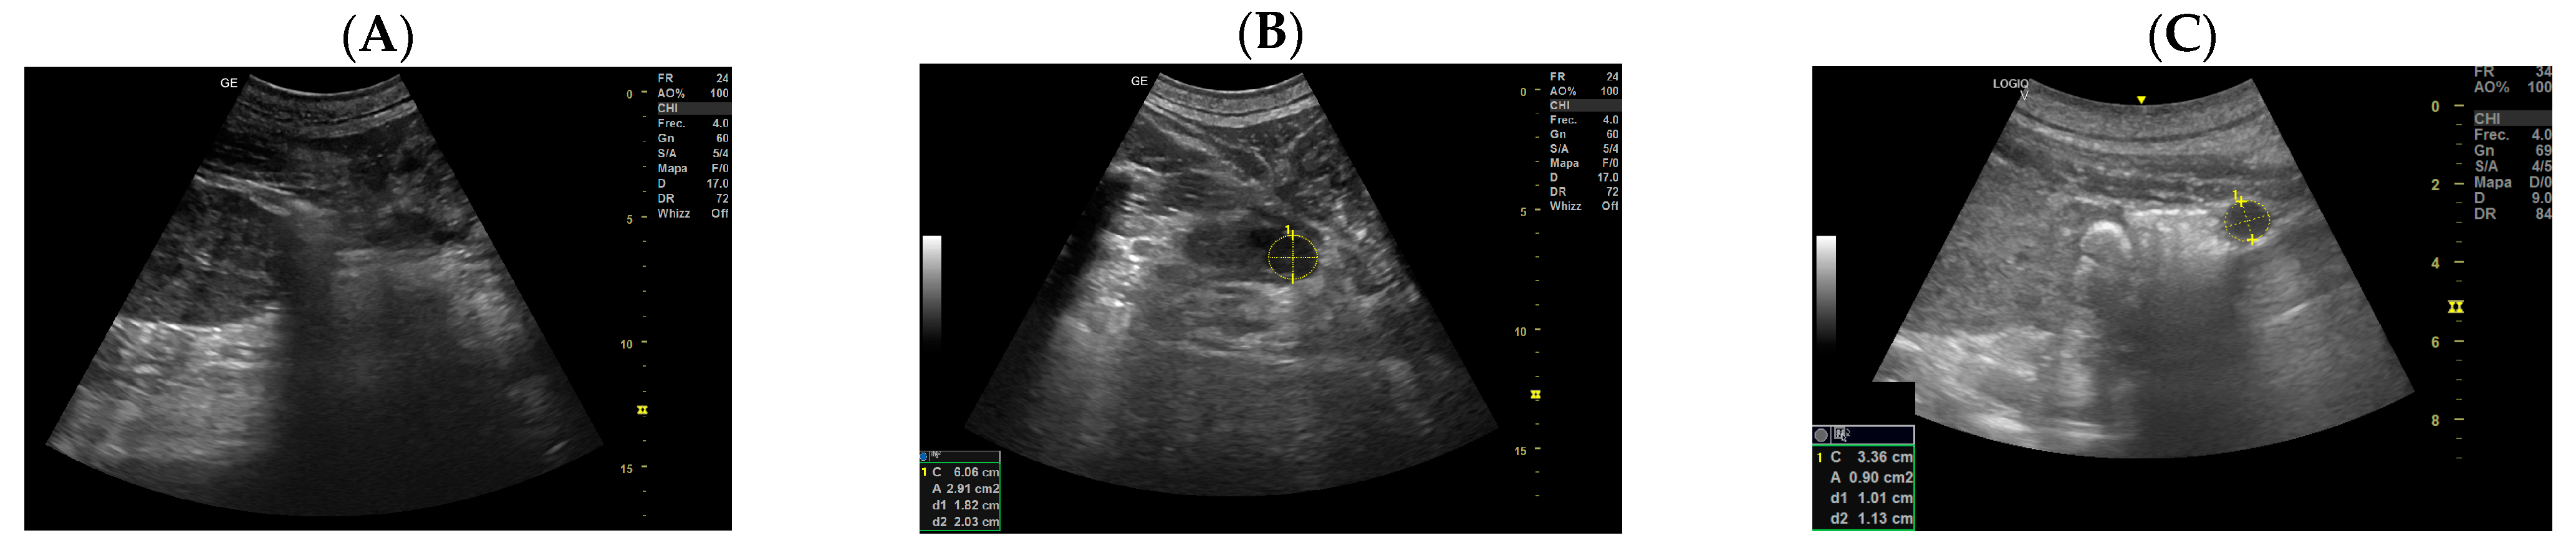

- Day 113 ± 4 post-ovulation: The embryonic vesicle was first recognizable in the uterine cavity as a roundish structure with an average diameter of 1.71 cm with an anechoic content. In addition, it is possible to recognize the embryo inside it as an elongated hyperechoic structure (Figure 2). Thanks to these findings, it has been possible to make a diagnosis of pregnancy.

- Day 219 ± 3 days: It is also possible to recognize the eye as an anechoic cavitary structure (Figure 6). During the last month of pregnancy, it is possible to easily identify most of the abdominal organs such as the liver, spleen, intestine, and kidneys (Figure 7). In addition, the genitalia are visible and it could be possible to establish the sex of the fetus: in males, it is possible to identify the penis bone, which is obviously absent in females, but its visualization depends strongly on fetal position.